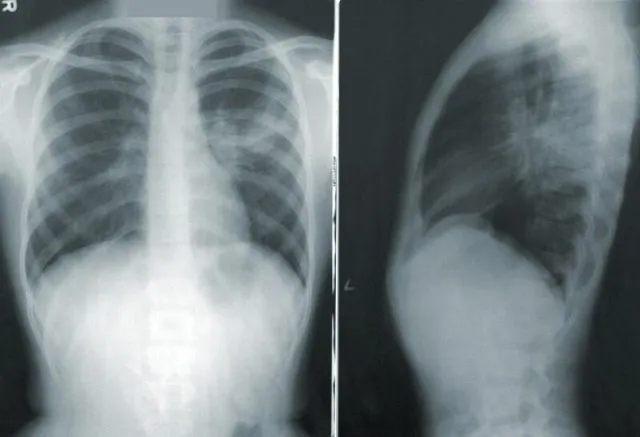

Istnieje wiele metod badań organizmu człowieka, jedną z nowocześniejszych jest teleradiologia, dzięki której diagnozowanie można wykonywać w sposób zdalny. Mogą z niej korzystać nie tylko duże ośrodki medyczne, szpitale i kliniki, ale nawet pojedyncze gabinety lekarskie.

Działanie systemu teleradiologii oparte jest na dwóch odgałęzieniach, jednym z nich jest jednostka centralna, a drugim przyłączone do niej placówki medyczne. Centra opisowe zarządzają całością, a placówki medyczne dodają do sieci wykonane obrazy diagnostyczne, które są opisane przez specjalistów. Szpitale lub gabinety podłączone do sieci zamieszczają w systemie radiologicznym obrazy diagnostyczne, które są przesyłane do jednostki centralnej i tam opisywane przez osoby do tego uprawnione, albo przekazywane dalej. Do wykonania opisów zatrudniani są wyspecjalizowani radiologowie. Działanie systemu polega na tym, aby wszystkie jednostki medyczne zlecające opisy mogły je jak najszybciej uzyskać, niezależnie od tego, w jakiej części kraju się znajdują. Jest to dobre rozwiązanie, które wpływa na komfort pracy lekarzy oraz jakość leczenia pacjentów, ponieważ znacznie szybciej można uzyskać wyniki i diagnozę schorzenia. Teleradiologia jest coraz bardziej popularnym rozwiązaniem, ponieważ wiele placówek medycznych nie może sobie pozwolić na zatrudnienie specjalisty radiologa. Właściwy opis i ocena wykonanego badania musi być wykonany przez doświadczonego profesjonalistę.